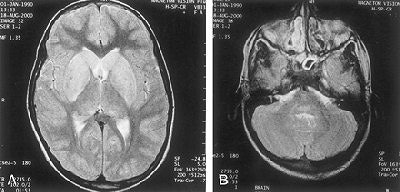

MR imaging was performed on a 1.5-tesla Magnetom Vision Plus scanner (Siemens Medical Solutions, Erlangen, Germany). Axial T2-weighted images showed hyperintensity involving central gray matter of the whole spinal cord, extending cranially to symmetrically involving the bilateral thalami, hippocampi, basal ganglia, and the dorsal aspect of the brainstem. A T2-weighted image at the level of the basal ganglia revealed hyperintensity of the caudate head and lentiform nucleus; another T2-weighted image done at the level of the pons showed hyperintensity of the posterior portion of the pons.

| A T2-weighted MR image of the brain (A), scanned at the level of basal ganglia. The exam reveals hyperintensity of the caudate head and lentiform nucleus. In image B, the T2-weighted MR image obtained at the level of the pons reveals hyperintensity of the posterior portion of the pons. Images courtesy of the Dr. Sunit Singhi. |

"Rabies has an affinity for bulbar and limbic neurons and specifically involves the brainstem," the group wrote. "In the cases of silent rabies, the most striking pathologic changes are seen in the spinal cord...MR images showed the predominant gray matter involvement of brain and spinal cord, which is a hallmark of rabies and an important differentiating point from acute disseminated encephalomyelitis."

The hyperintensity of spinal cord gray matter on the T2-weighted images corresponds to inflammatory cell infiltration, they concluded.